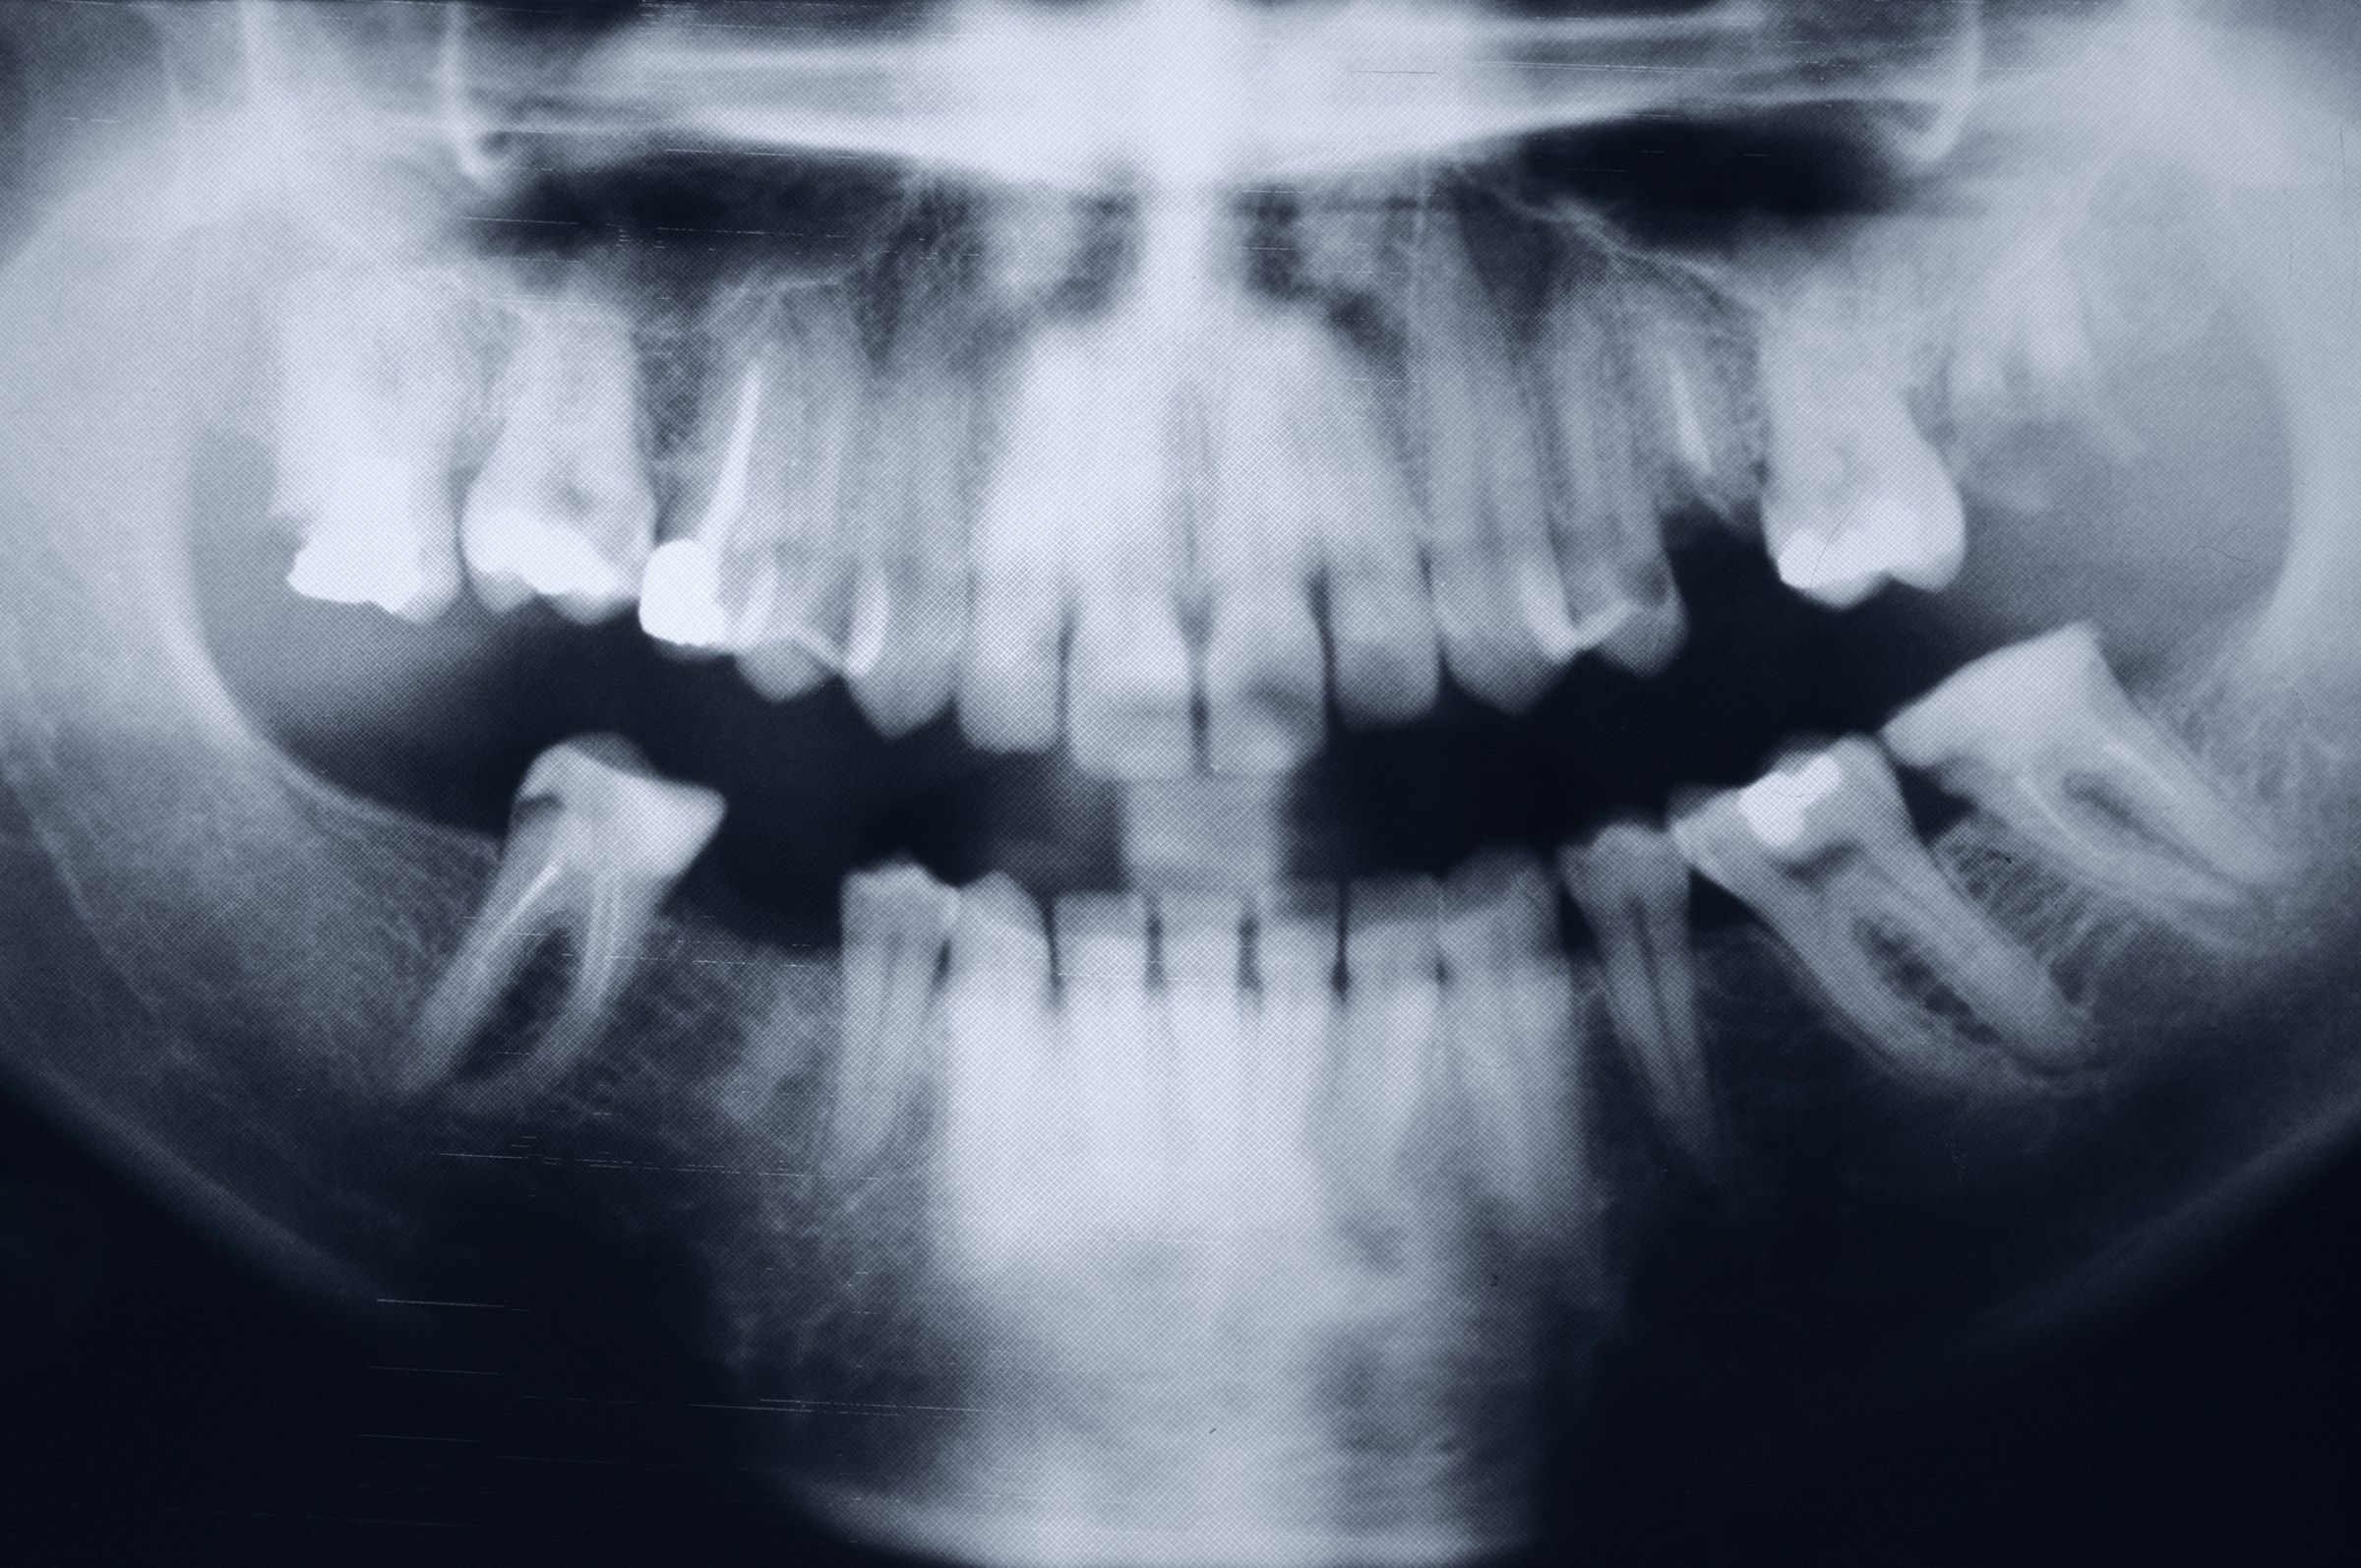

Surgical orthodontics is a combined treatment approach that involves both orthodontic care and jaw surgery to correct severe irregularities in jaw alignment, facial asymmetry, and bite problems. This specialized treatment helps improve both the functional aspects of your bite and the aesthetic appearance of your face.

Surgical orthodontics may be recommended for patients with:

- Severe overbite or underbite

- Significant open bite

- Asymmetrical jaw growth

- Difficulty speaking, eating, or breathing

- Sleep apnea related to jaw position

- Facial imbalance